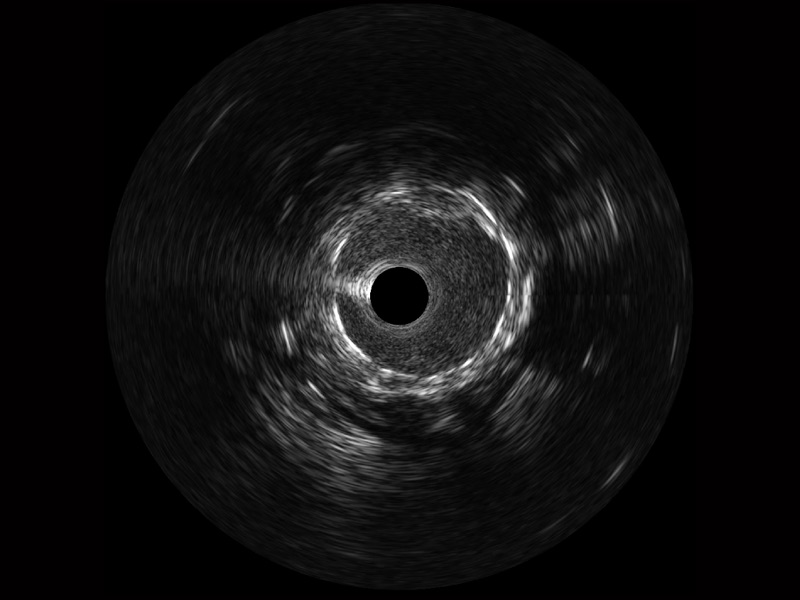

米兰官方网站宽频IVUS图像

对比传统IVUS导管成像,米兰官方网站宽频IVUS图像的近场支架梁显影更细腻,远场中膜外血管仍清晰可辨,兼顾远中近,兼顾分辨力与穿透深度